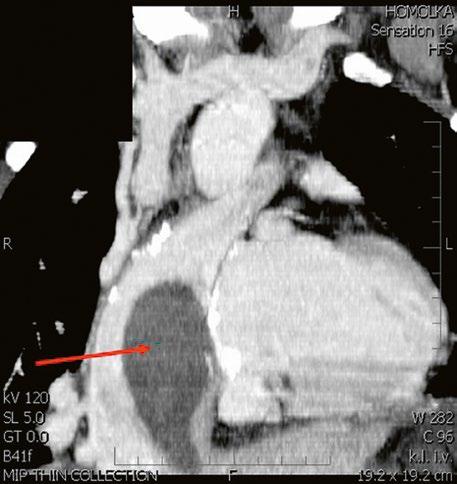

Obr. 45.11 CT angiografie, defekt typu sinus venosus superior je označen hvězdičkou, anomální pravá horní plicní žíla ústící do horní duté žíly je označena šipkou

PS – pravá síň, LS – levá síň